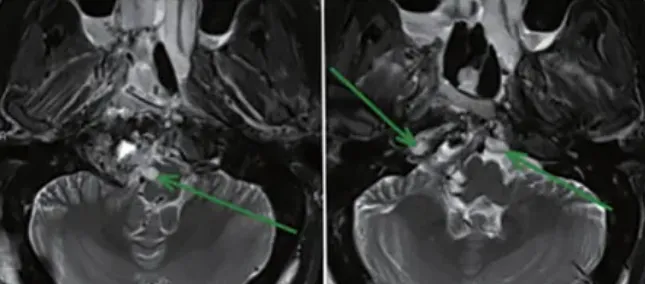

▼晓亚第4次复发后的MRI,也是福教授所面临的复杂状况

肿瘤位于下斜坡,并向周边广泛延伸,右侧C1和C2、岩尖水平均见有肿瘤,右侧椎动脉被肿瘤包绕,脑干受压迫,软脑膜平面、后循环血管及骨质均已被肿瘤广泛浸润。要知道,这些区域并非畅通无阻,中间充斥着许多碰不得的神经血管“红线”,肿瘤并不能被一次性完整剥离。

▼第一阶段经鼻内镜手术结束,正中中线部分肿瘤成功切除,其他残留肿瘤等待第二阶段开颅手术切除(绿色箭头)。